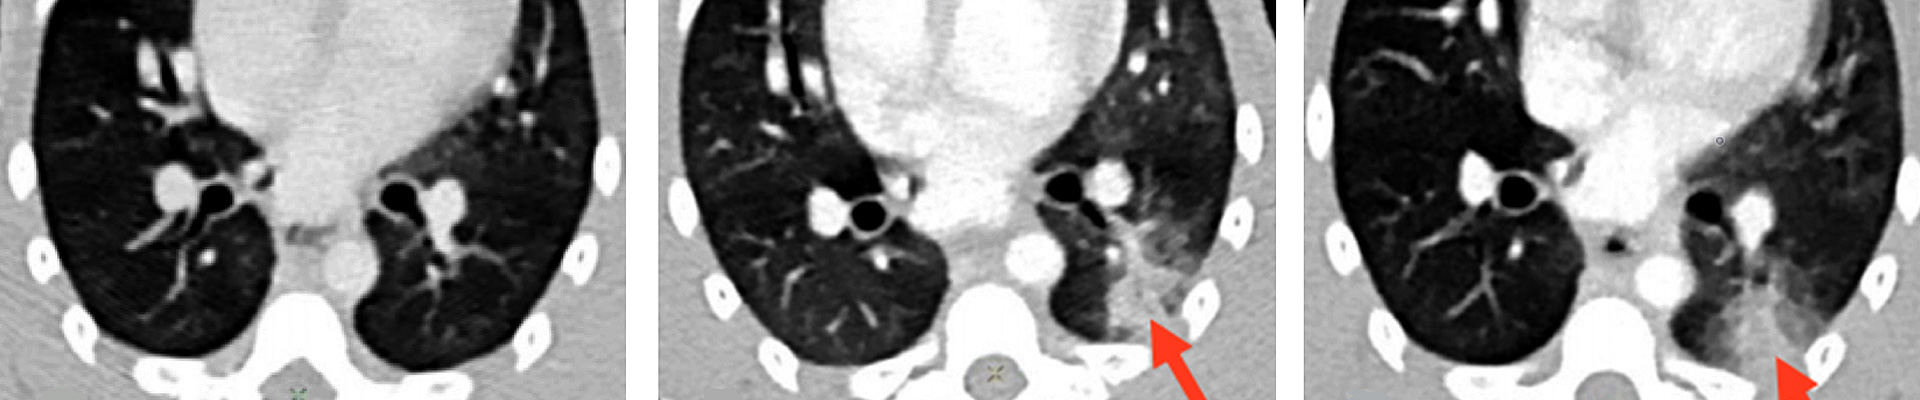

De la tuberculose au VIH / SIDA, les équipes d’IDMIT mènent des recherches sur différentes maladies infectieuses, participent au développement de traitements et de vaccins. L'expertise acquise au fil des années leur a permis d'être préparées pour répondre à l'urgence de la pandémie de Covid-19.